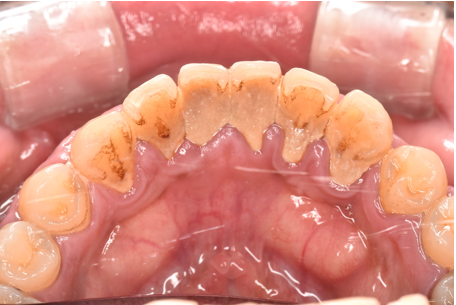

general 20代男性「歯周病治療と歯石を除去したい」中等度の歯周炎に歯石除去と歯周病治療を行った症例

| カウンセリング・診断結果 | 診察したところ、全体的に歯石が付着していて、特に歯茎の下には黒い歯石が付着していました。 歯茎も赤く腫れており、歯周病の検査を行ったところ、全体的に歯周病が進行し、中等度の歯周炎が認められました。 |

| 行ったご提案・治療内容 | 初診時に撮影したレントゲン、口腔内写真、歯周病検査の結果を用いて、歯周病治療の必要性をお伝えしました。 初診時は歯ブラシの使い方などセルフケアの方法をご説明し、その後に歯肉縁上歯石(歯肉より上に付く黄色または乳白色の歯石)を除去しました。 歯肉の炎症がある程度落ち着いた後日、再評価を行い、歯周治療へ移行しました。 |